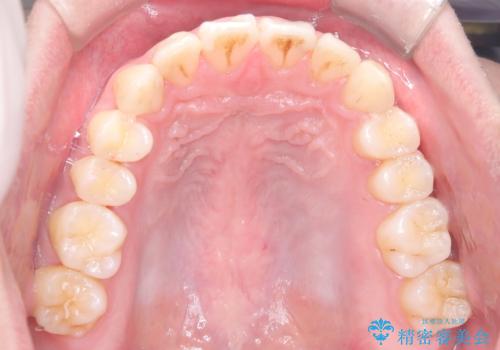

- 前歯が出ていることを主訴に来院されました。

歯列の幅が狭かったため、横に広げながらスペースを作り、叢生の改善を行いました。

左側の犬歯関係も治療前より良い状態で治療を完了することができました。